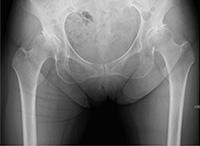

手术前X线图像

手术后X线图像

关节软骨磨损,关节的缝隙变窄,白色部分为人工关节。